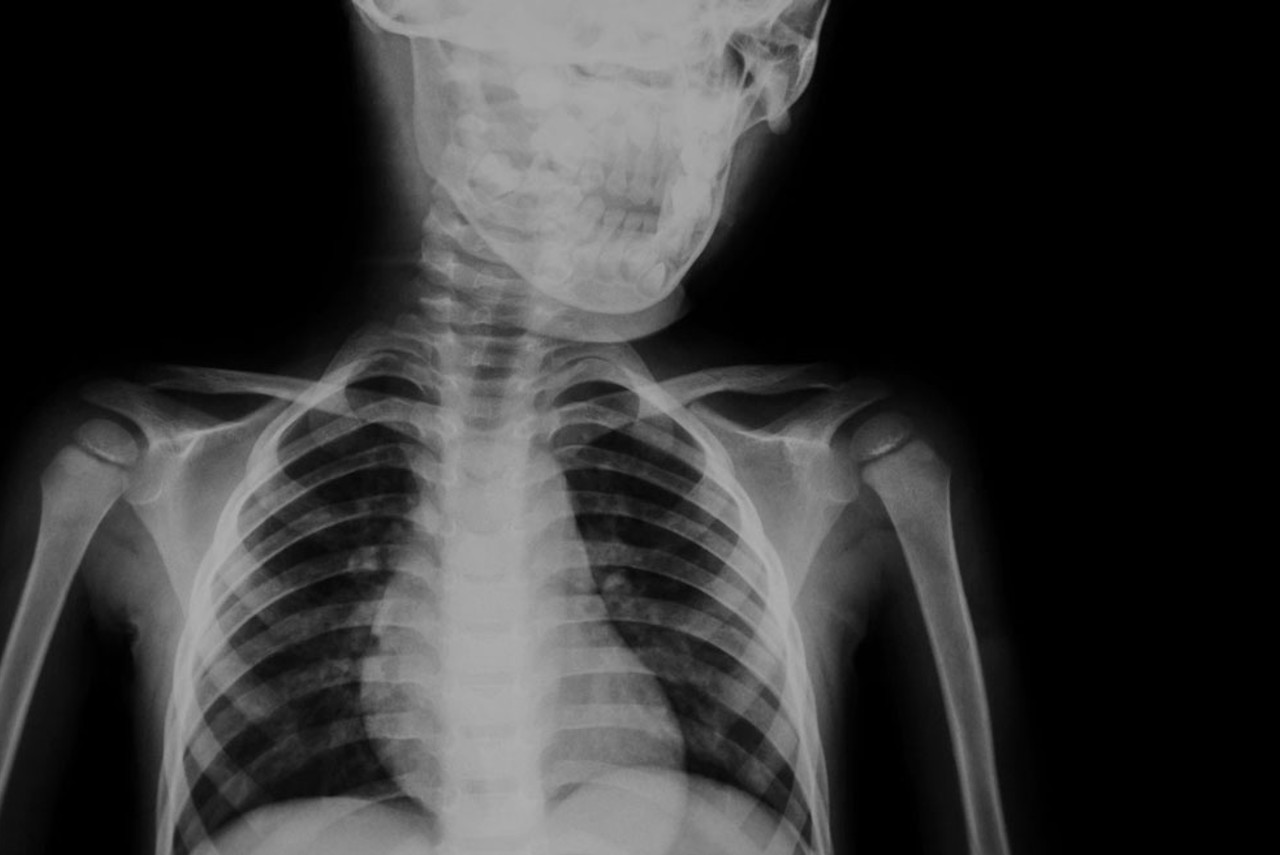

An X-ray image is created when a small amount of radiation is passed through a body part. Different internal structures absorb different amounts of radiation, which is why the end result of an X-ray shows the white solid bone structures and grey muscle areas.

- Diagnosis of chest and lung conditions such as pneumonia